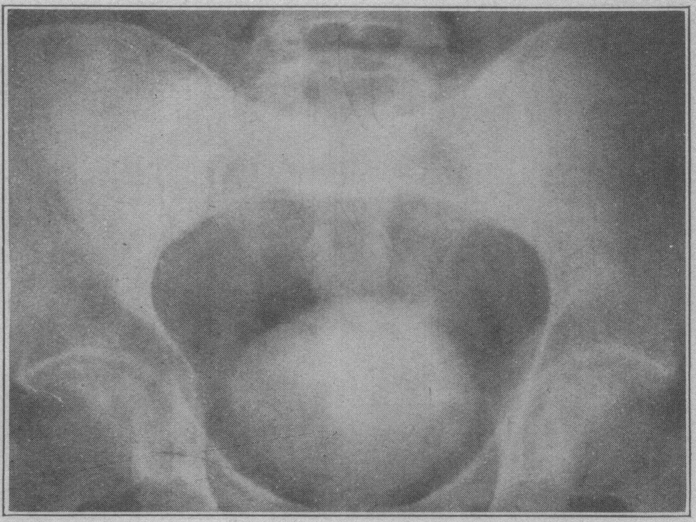

Initial investigations of sodium iodide also included a radiologist named Charles Sutherland and a urologist named Albert Scholl and were published in JAMA in February of 1923. The image on the left is from that paper, taken two hours after the administration of 200 cc of a 20% solution of sodium iodine showing opacification of the bladder. The roentgenogram on the right was taken about an hour after the administration of 100 cc of a 10% solution. You can see that the bladder is opacified, and there’s faint opacification of the kidneys, spleen, and liver. Ironically, neither Dr. Osborne nor Dr. Rowntree pursued this any further, but Dr. Osborne did go on to help found the American Board of Dermatology.